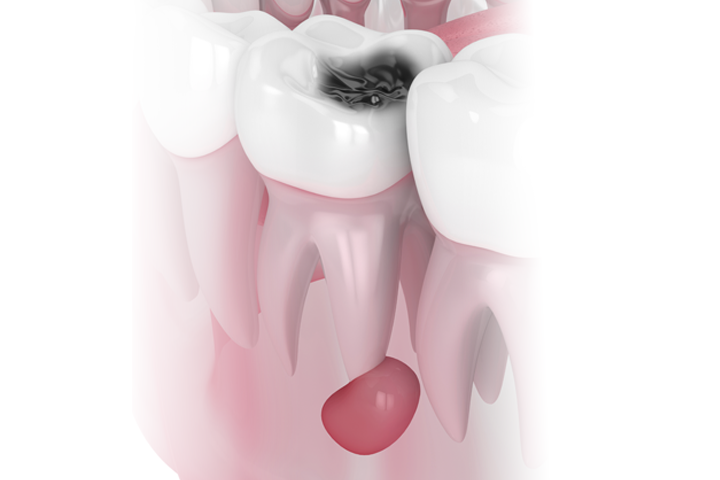

Quistes Maxilares

Los quistes a nivel de los maxilares son una alteración relativamente frecuente, de etiología benigna, y de fácil resolución. Sólo en casos muy poco frecuentes, estos quistes ya sea por el tamaño o por el tipo de tejido pueden comportar secuelas más graves como pérdida de dientes, de tejido óseo o incluso invadir estructuras vecinas.

Síntomas quistes en la boca

Los quistes en la boca no provocan dolor ni molestias, por lo que es necesario detectarlo mediante una radiografía. Es solamente cuando el quiste es de gran tamaño que podremos notar ya un dolor agudo e intenso así como una inflamación en el hueso que puede llegar a mover los dientes de la boca.